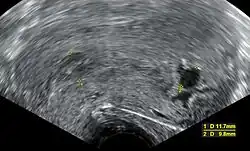

| An ultrasound showing a gestational sac containing a yolk sac but no embryo | |